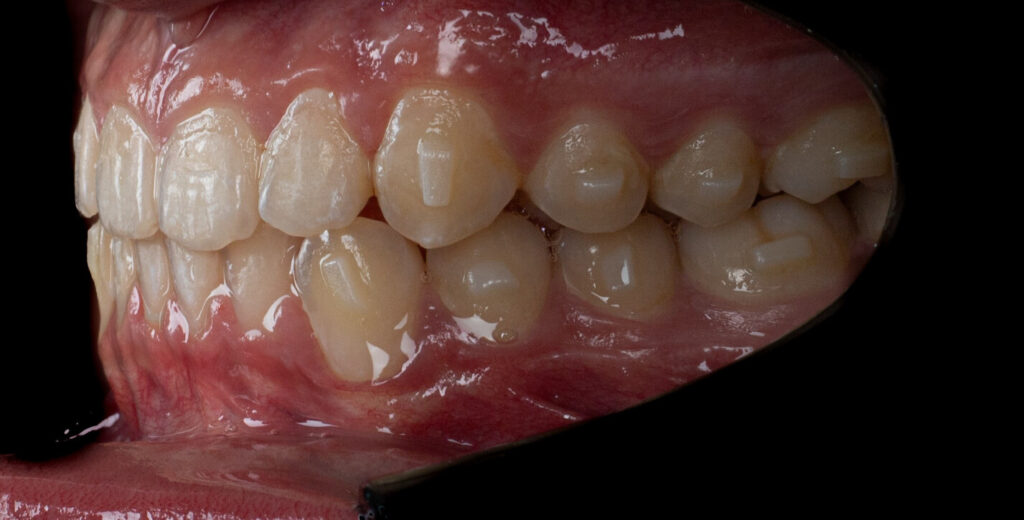

Um paciente do sexo masculino, com 13 anos de idade, apresentou-se com uma mordida profunda, caracterizada pela cobertura quase completa dos incisivos mandibulares. A avaliação clínica revelou apinhamento em ambas as arcadas, rotações dentárias e proclinação dos incisivos laterais superiores, contribuindo para as preocupações estéticas do paciente. O perfil facial era retrusivo, consistente com retrognatismo mandibular, e não foram detectadas anomalias periodontais significativas.

O paciente apresentava uma relação esquelética de Classe II com molares e caninos bilaterais em Classe II e um padrão dentário de Classe II divisão 2. A mordida profunda estava associada a um apinhamento anteroinferior e a uma curva de Spee acentuada. A análise facial revelou boa simetria, um terço facial inferior ligeiramente aumentado e um perfil convexo caracterizado por retrusão mandibular e do mento. A competência labial estava ligeiramente reduzida, com diminuição do ângulo nasolabial e leve tensão do músculo mentoniano, fatores que comprometiam a harmonia facial global.